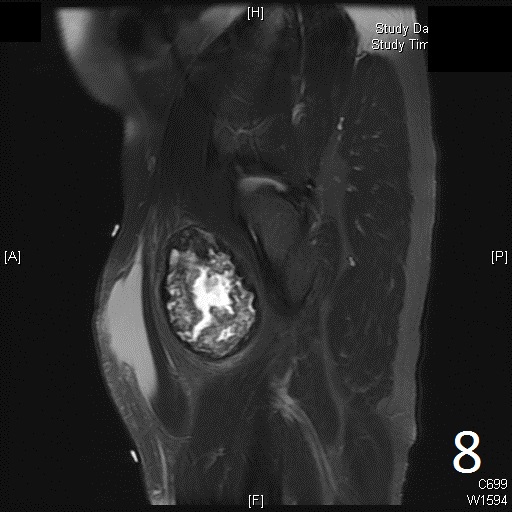

• 60% of fibrosarcomas are intramuscular (Fig. 2, 3, 5, 6, 7, 8)

• Well defined heterogenous mass on T2W (Fig. 4, 9)

• Necrosis and hemorrhage are common, especially in high grade tumors

Fig. 5-9: Axial and sagittal (Fig. 6) MRI shows a fibrosarcoma in the proximal quadriceps muscle that is isointense to muscle on T1W images, and a heterogeneous on T2W FS (Fig. 7, 8). The patient was treated with preoperative chemotherapy and the mass underwent extensive necrosis. The mass does not show any enhancement with contrast due to the extensive necrosis. There is only peripheral enhancement with contrast on T1W FS (Fig. 9).